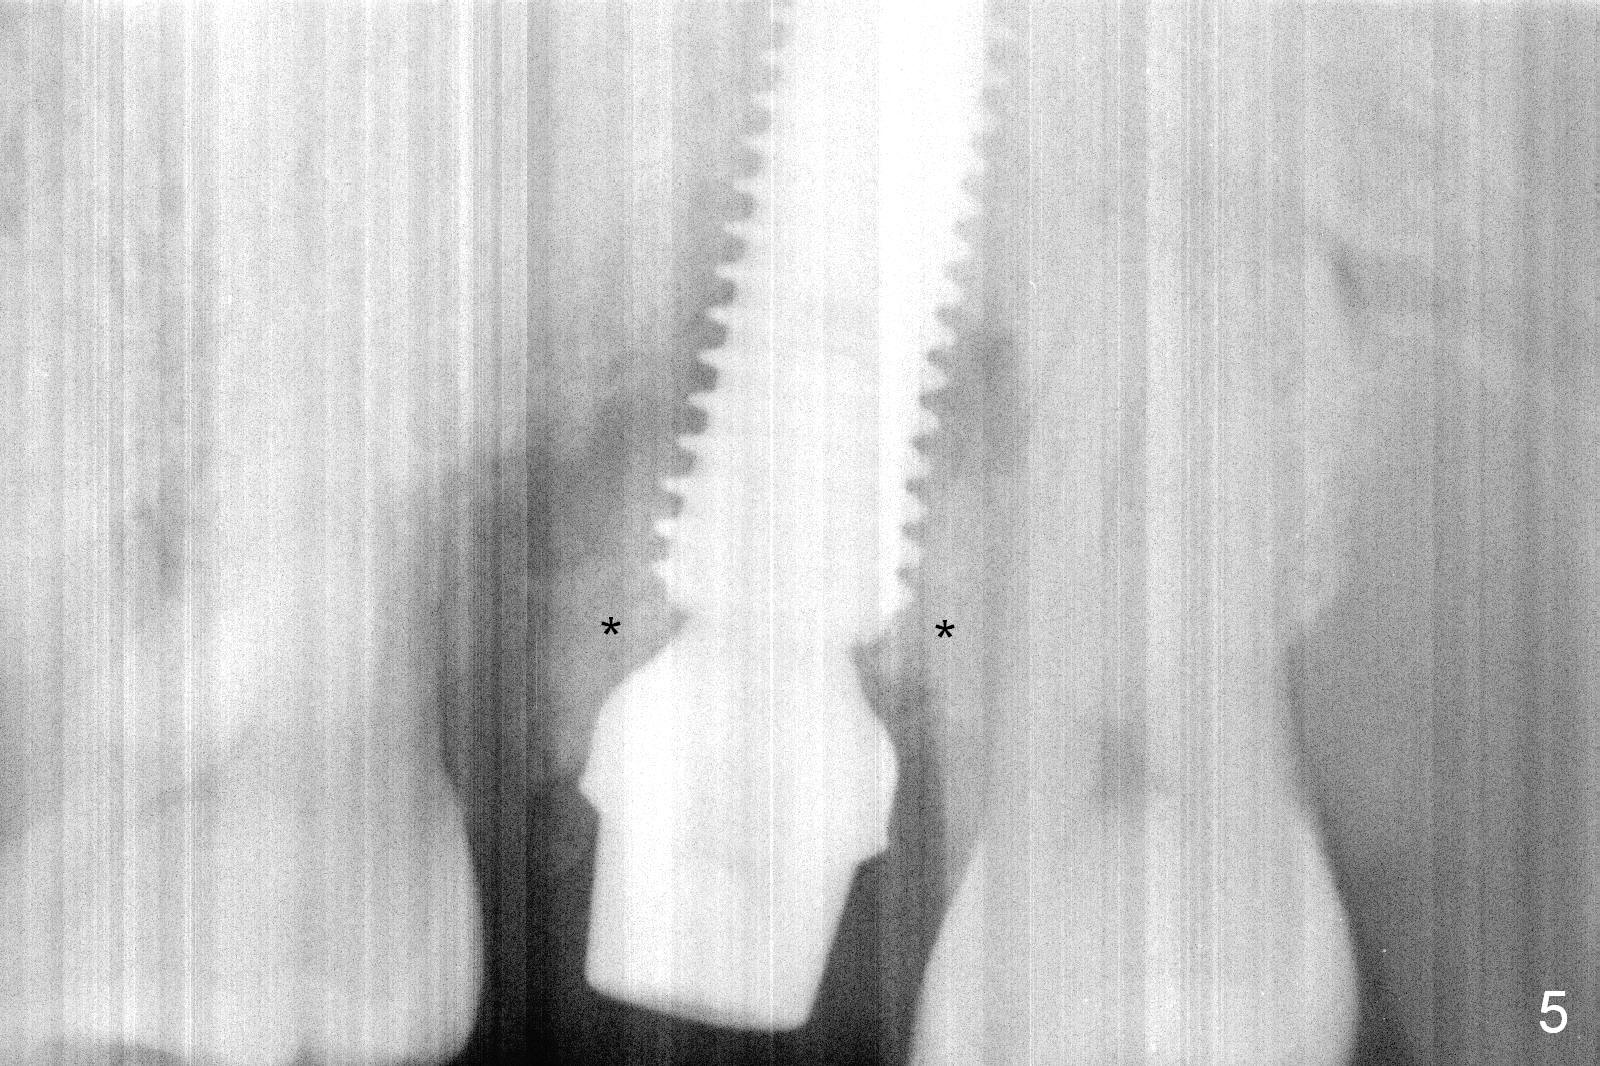

When the tooth #15 is extracted, the buccal plate is found to have been lost. The depth of osteotomy in the native bone is 8.5 mm (Fig.1,2). When a 5.5x15 mm implant is placed (Fig.3), the insertion torque is > 55 Ncm. The implant is palatally placed with a 10x10 mm Osteogen plug being placed in the deep portion of the buccal gap for buccal plate repair (Fig.4 *). The superficial portion of the remaining socket is filled with .5-1.5 mm allograft/autogenous bone/Osteogen (Fig.5 *). The drawback of this procedure is that the abutment is placed prior to placement of the graft. The latter fails to reach the deepest area of the defect. If periimplantitis develops because of insufficient graft, do it again in due time.